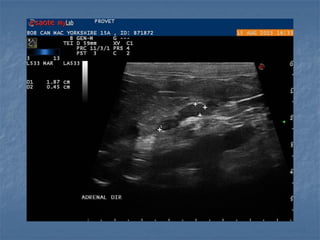

Hiperplasia adrenal unilateral